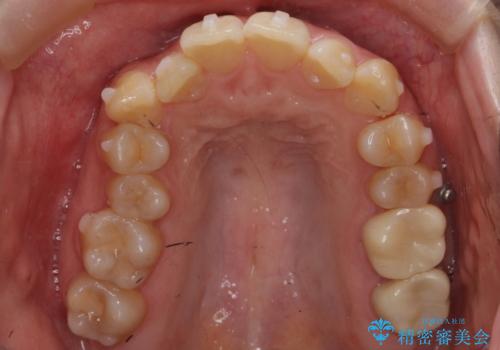

- 前歯の並びと下の歯のがたつきを主訴に来院。

左下にがたつきが集中していました。

歯を抜かずに、左上および左下の奥歯を後ろに送ることで隙間を確保しました。

左下の第一小臼歯が歯列からはみ出て、近心傾斜しており、抜歯の上ワイヤー矯正の選択肢もお話ししましたが、非抜歯で、インビザライン矯正を希望されました。左下の第一小臼歯は完全に並べることは難しいと初めから説明し、納得いただいた上で治療開始しました。